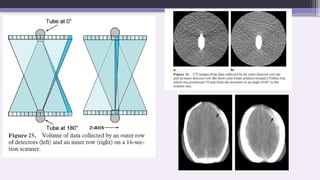

2. Cone Beam Effect:

As the number of sections acquired per rotation increases, a wider

collimation is required and the x-ray beam becomes cone-shaped

rather than fan shaped.

As the tube and detectors rotate around the patient the data collected

by each detector correspond to a volume contained between two cones,

instead of the ideal flat plane.

Small structure, such as piece of bone is detected by beam from

one direction but is missed by opposing beam resulting

inconsistency , leads to streak artifact

This leads to artifacts similar to those caused by partial volume

around off-axis objects. The artifacts are more pronounced for the

outer detector rows than for the inner ones where the data collected

correspond more closely to a plane.



Reconstruction techniques like axial multiplanar

reconstruction (AMPR) are used that account for the cone

beam angle thereby reducing cone beam artifact

Cone beam Algorithms- FDK (Feldkamp Davis and Kress)

algorithms

Rebinning technique (transforming and reorganizing 3D projection

data into a 2D format to allow for faster and more efficient reconstruction

using existing 2D reconstruction algorithms)

Cone beam effects get worse for increasing numbers of detector

rows.

Thus, 16-section scanners should potentially be more badly

affected by artifacts than four-section scanners.

However, manufacturers have addressed the problem by

employing various forms of cone beam reconstruction instead of

the standard reconstruction techniques used on older scanners.